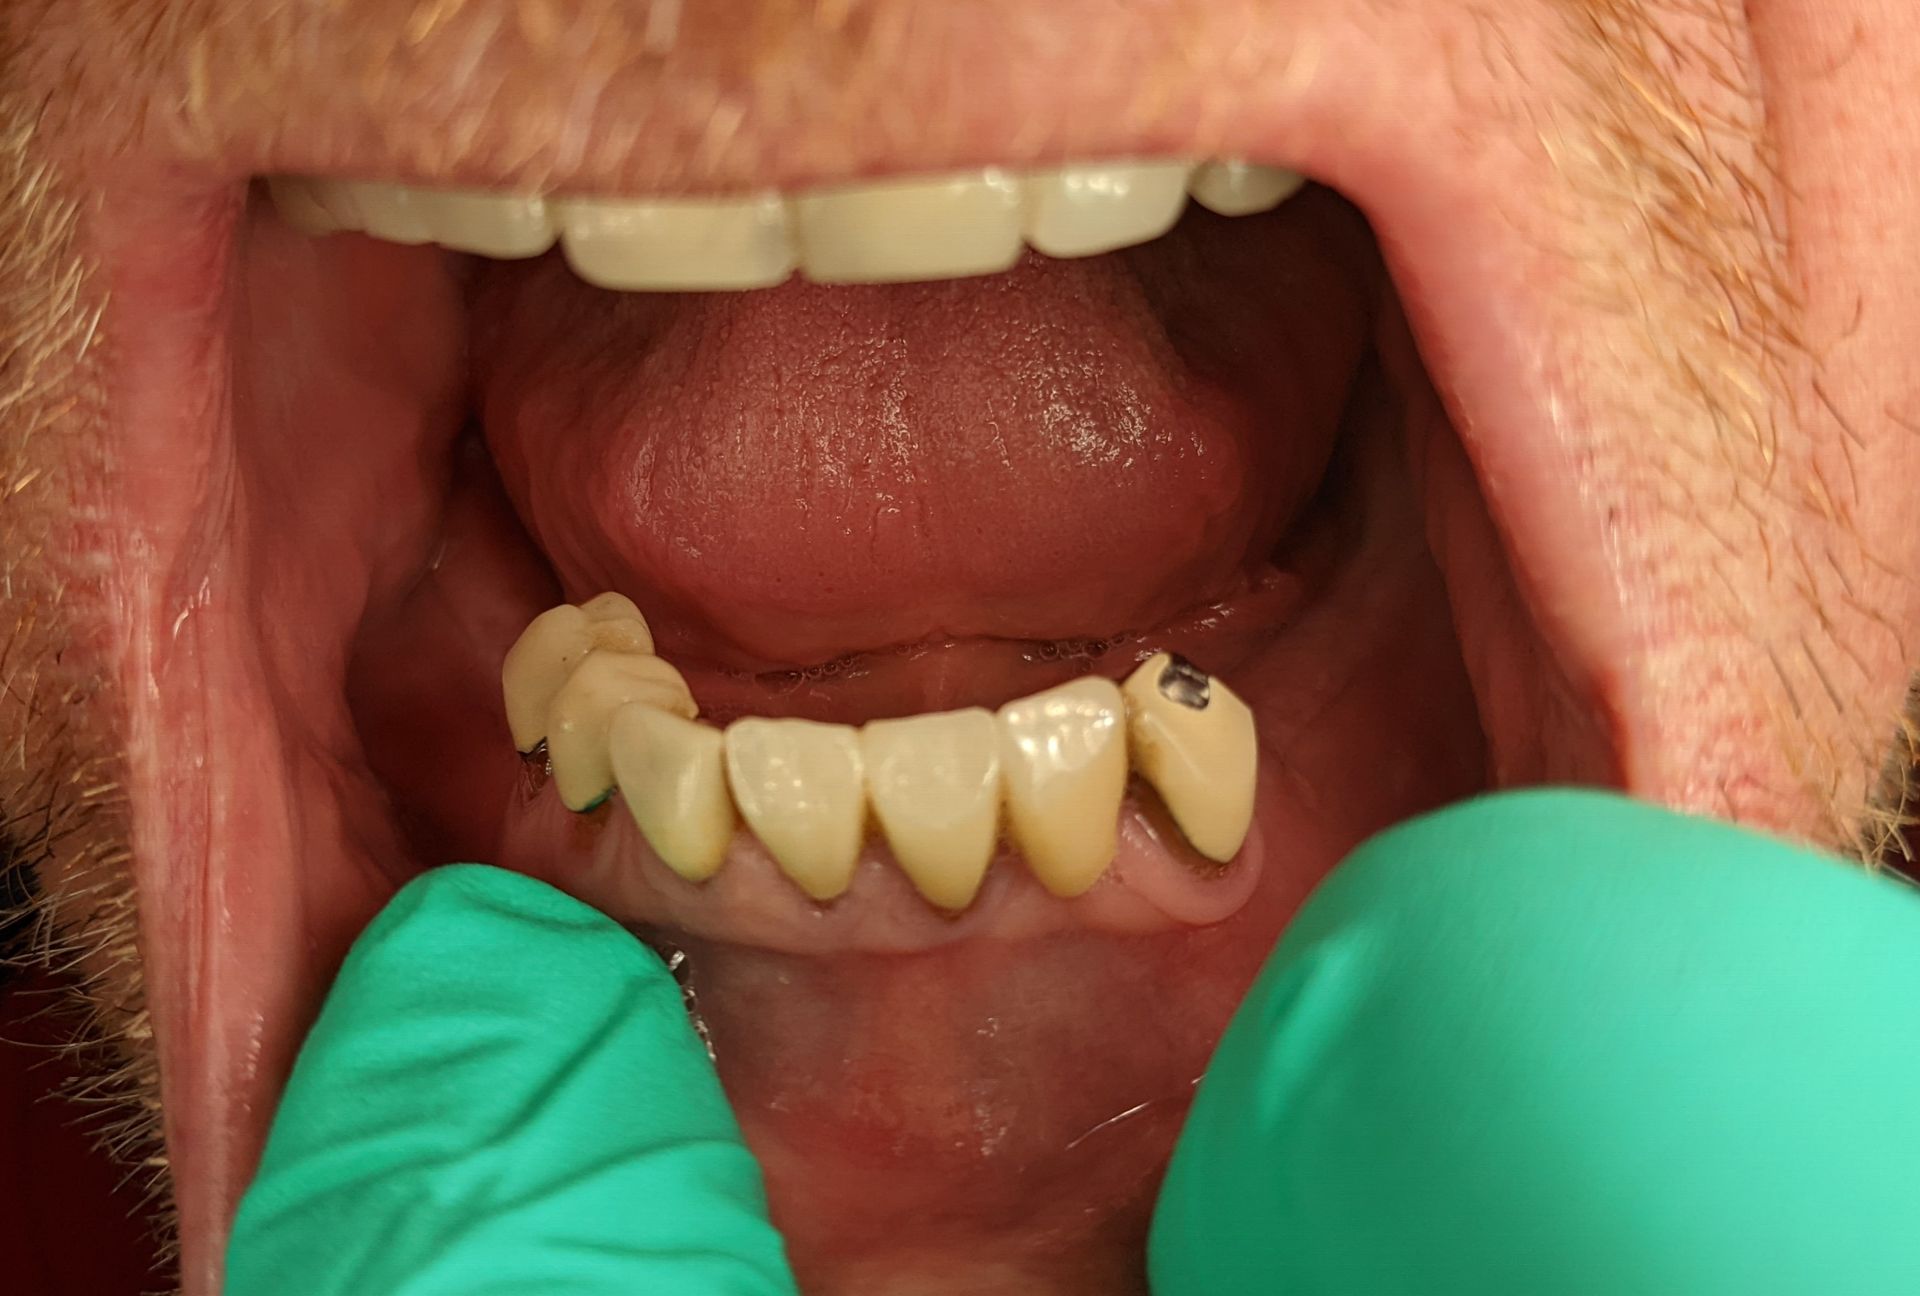

To fix teeth with crowns or bridges

Dental implants function as a permanent base to support crowns or bridges by providing a strong and enduring method for tooth restoration. The implants integrate with the jawbone to create a natural tooth structure which produces both strength and an attractive outcome.